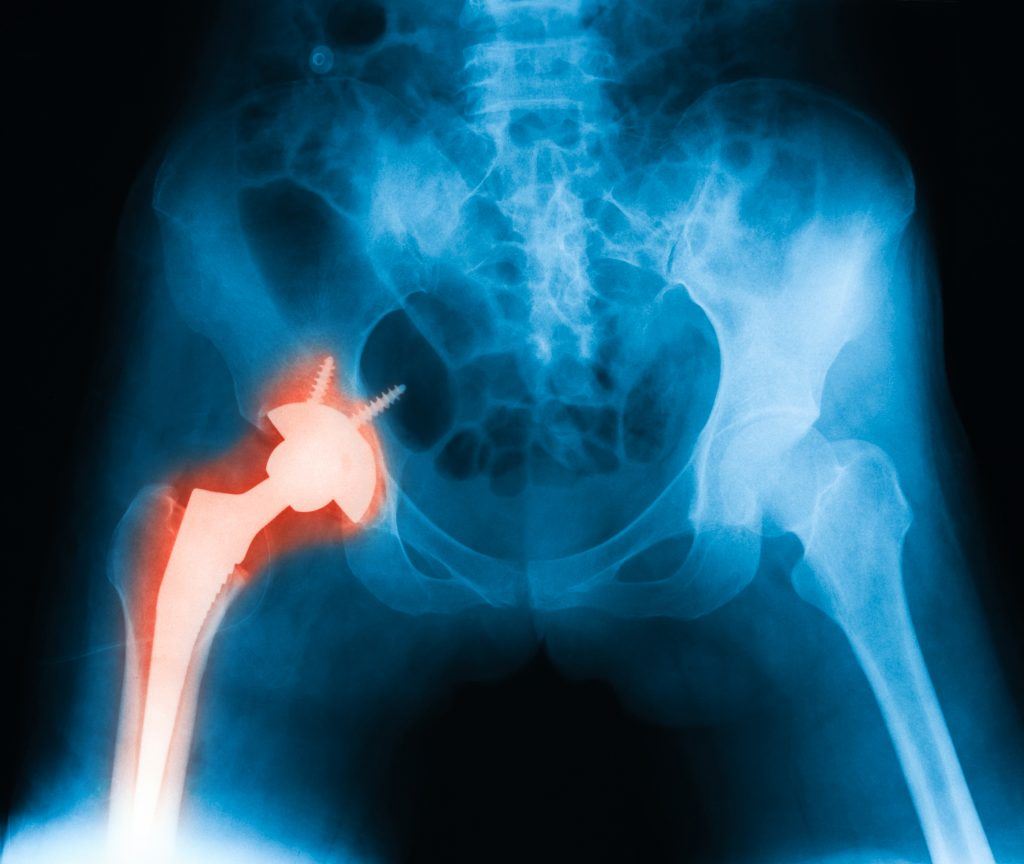

Once again, another hip replacement system is in the news. And the news is not good.

Stryker Corporation, one of the world’s largest manufacturers of medical equipment and orthopedic devices, is once again having problems with yet another of its hip replacement implants – the Stryker LFit V40 Femoral Head. It’s being reported that these Stryker devices may be vulnerable to corrosion and “fretting,” which allows minute shards of its metallic components to leach into a patient’s tissues, bones and/or bloodstream.